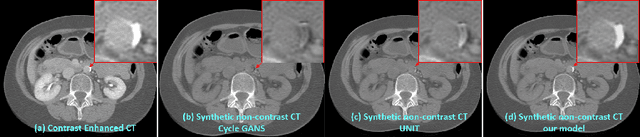

Abstract:Current deep learning based segmentation models often generalize poorly between domains due to insufficient training data. In real-world clinical applications, cross-domain image analysis tools are in high demand since medical images from different domains are often needed to achieve a precise diagnosis. An important example in radiology is generalizing from non-contrast CT to contrast enhanced CTs. Contrast enhanced CT scans at different phases are used to enhance certain pathologies or organs. Many existing cross-domain image-to-image translation models have been shown to improve cross-domain segmentation of large organs. However, such models lack the ability to preserve fine structures during the translation process, which is significant for many clinical applications, such as segmenting small calcified plaques in the aorta and pelvic arteries. In order to preserve fine structures during medical image translation, we propose a patch-based model using shared latent variables from a Gaussian mixture model. We compare our image translation framework to several state-of-the-art methods on cross-domain image translation and show our model does a better job preserving fine structures. The superior performance of our model is verified by performing two tasks with the translated images - detection and segmentation of aortic plaques and pancreas segmentation. We expect the utility of our framework will extend to other problems beyond segmentation due to the improved quality of the generated images and enhanced ability to preserve small structures.